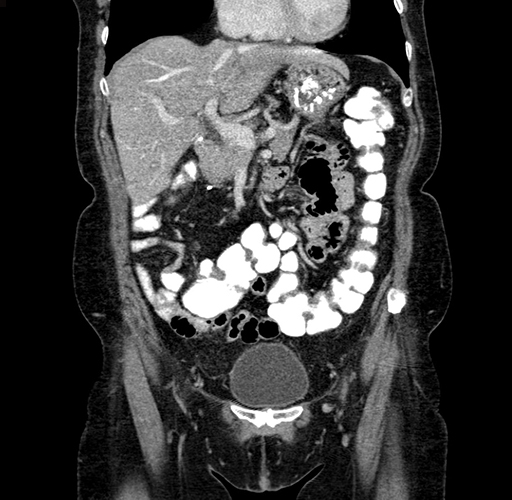

Pre-Chemo: Axial Venous

Pre-Chemo: Coronal Venous